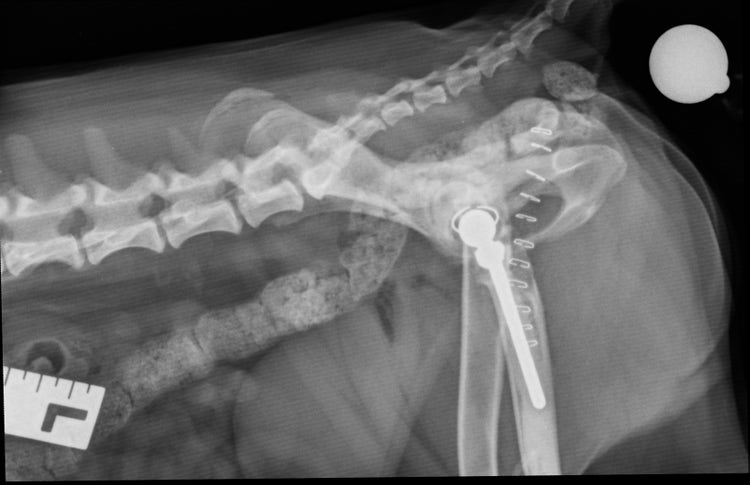

An x-ray of Barney's left hip after hip replacement surgery

The imaging results confirmed the worrying diagnosis: a complete dorsal luxation (dislocation) of the left hip, subluxation of the right hip, early bony remodelling of both femoral necks and significant muscle wastage. Without intervention, Barney faced a lifetime of severe pain, progressive mobility loss and poor quality of life.